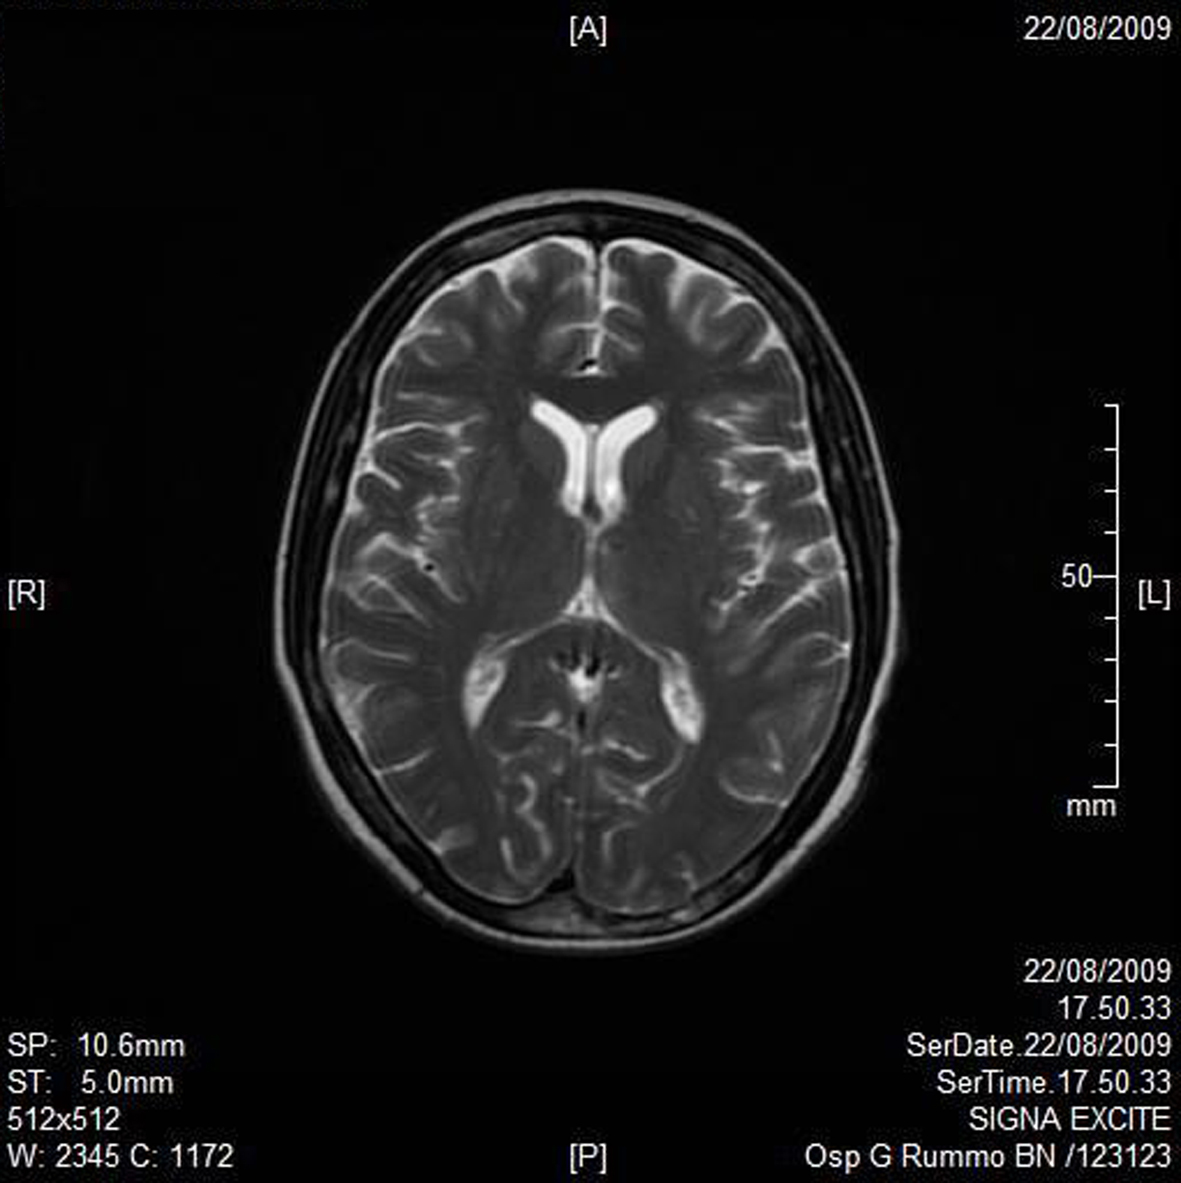

A RMN of the brain showed this clinical imaging (Fig. 1, 2) as a multinfartual area due to microembolization in blood vessels of the brain. The patient died after 10 days.

![]() Click for large image | Figure 2. Axial T2W imaging. |